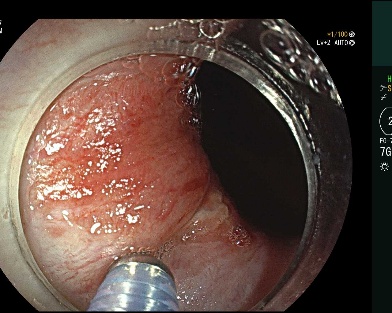

另一名35岁女性患者,初步考虑为内外混合痔,同时伴有严重脱出。孔德润团队综合评估后选择内镜下套扎术治疗。在内镜直视下,用特制器械将微型胶圈精准套扎于内痔根部,如同给气球扎口,切断血流使其自然萎缩脱落。